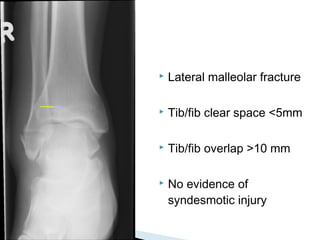

 Lateral malleolar fracture

 Tib/fib clear space <5mm

 Tib/fib overlap >10 mm

 No evidence of

syndesmotic injury